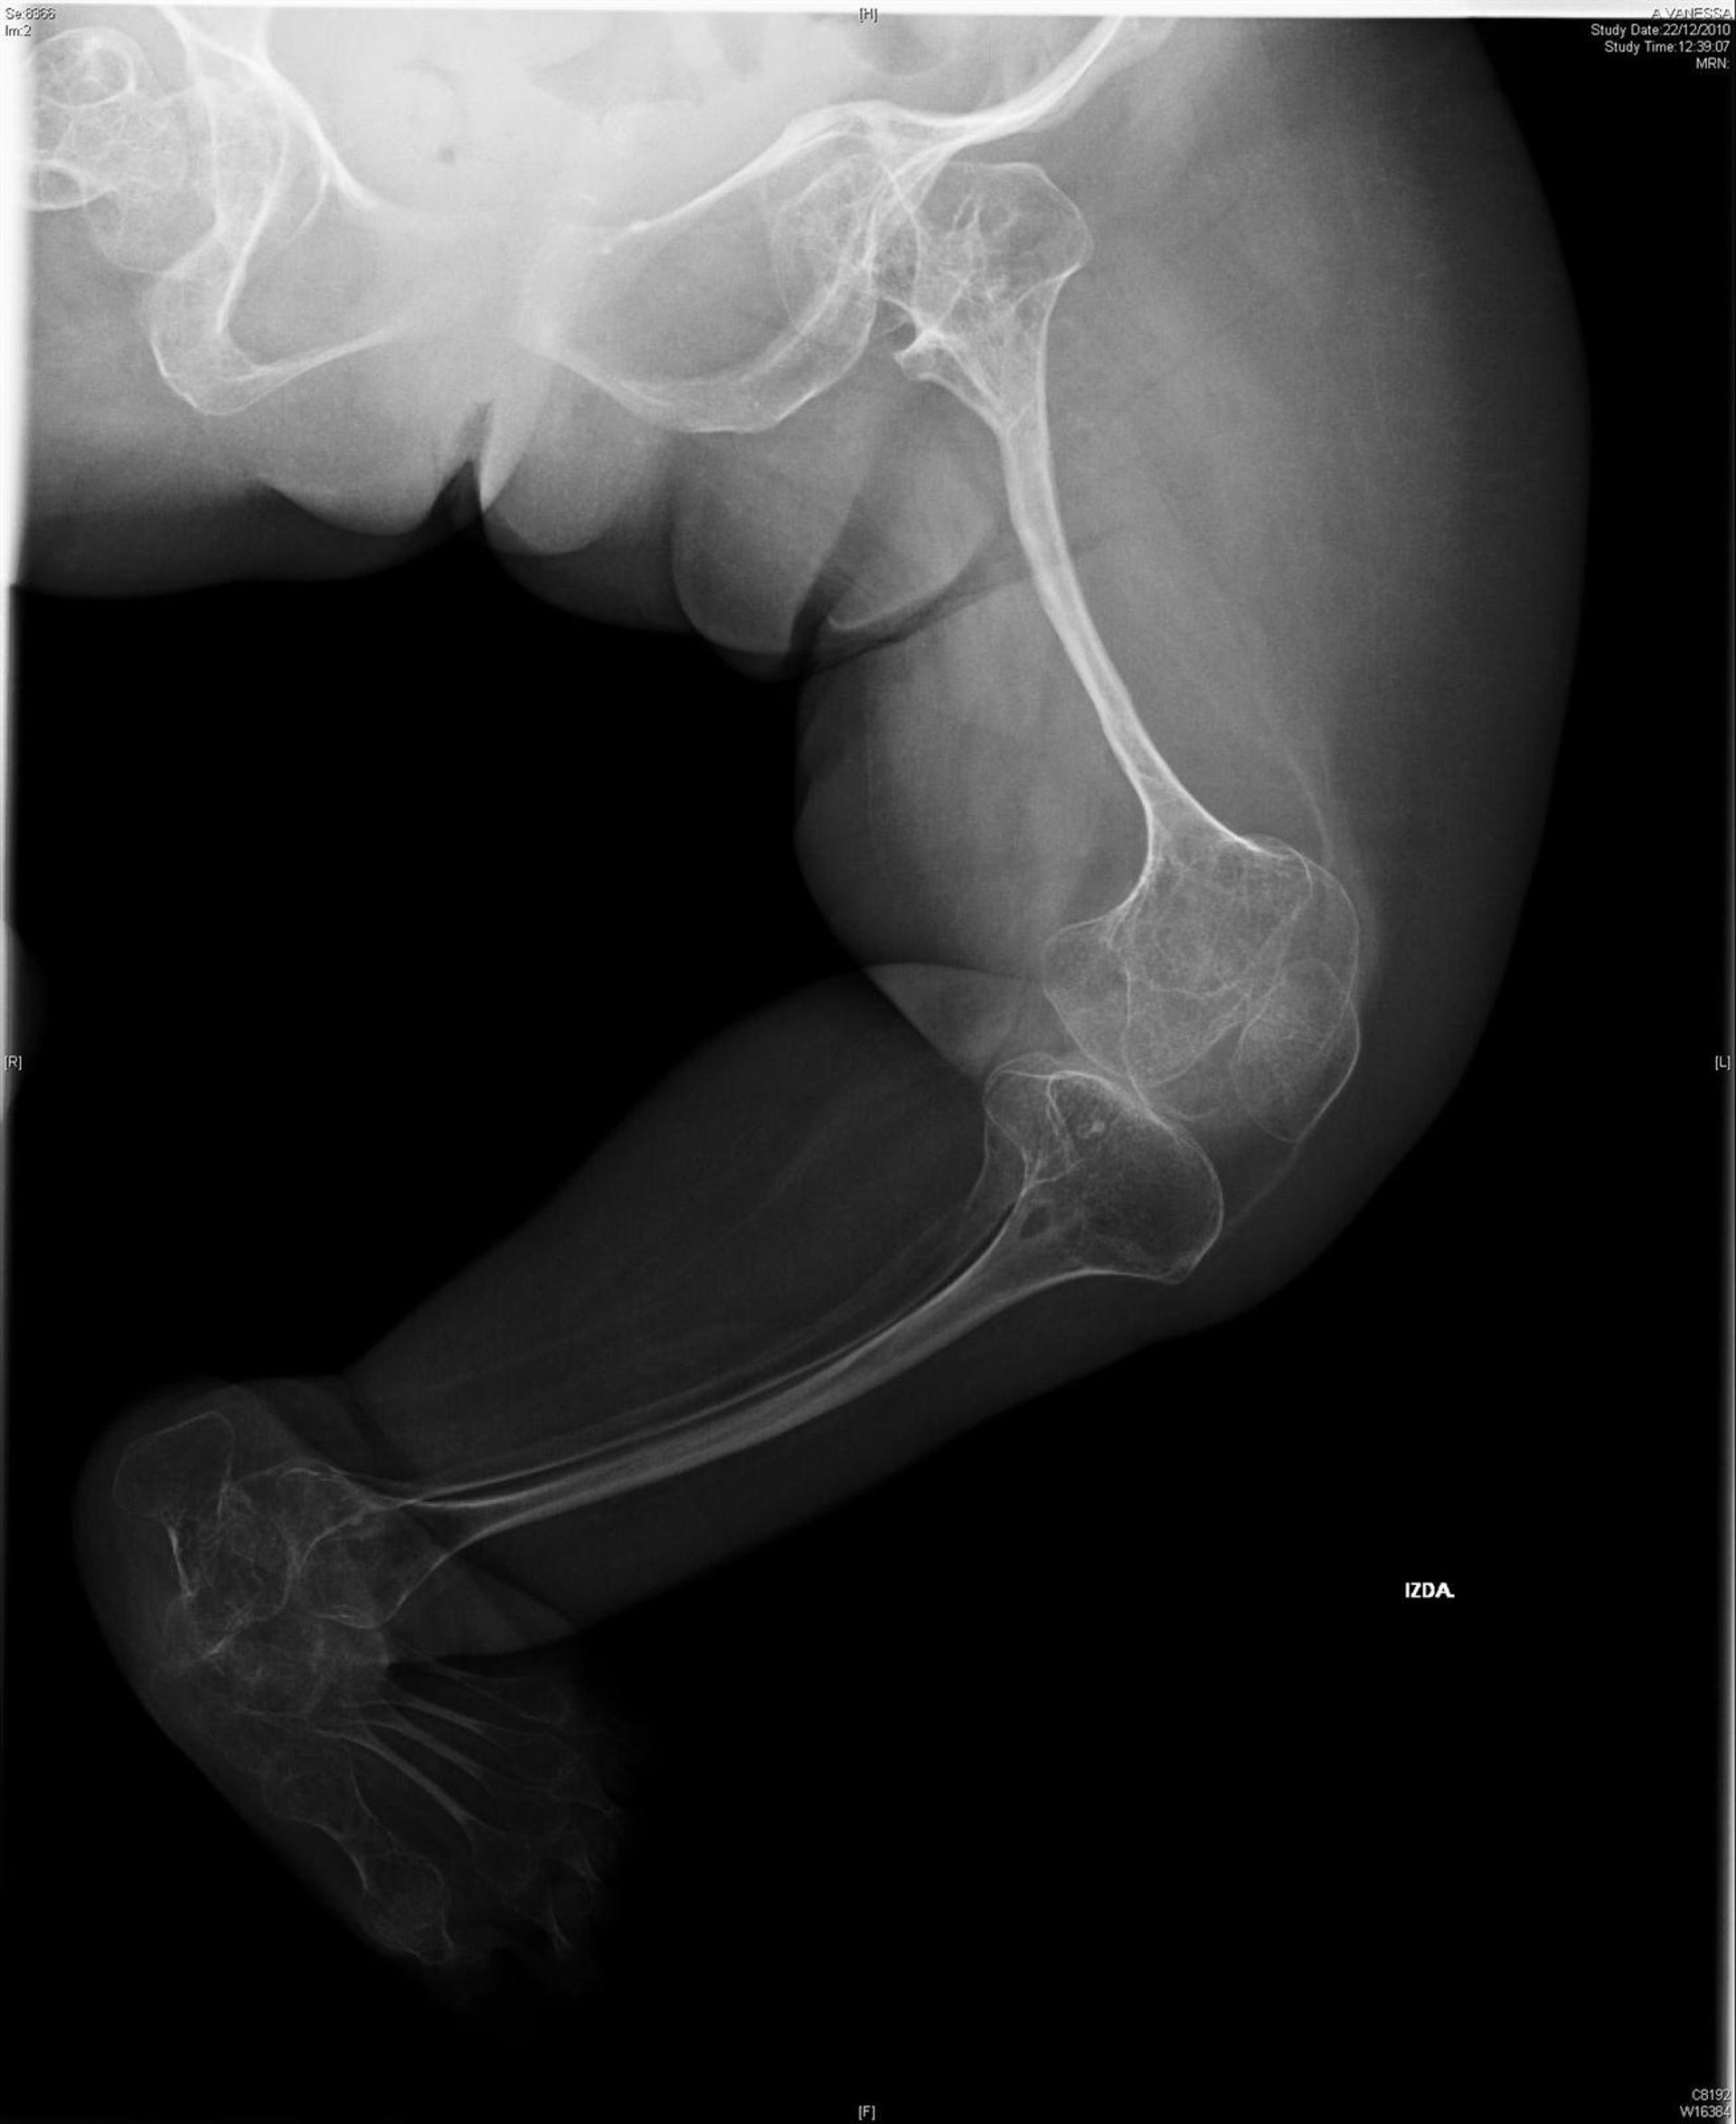

El uso de risedronato reduce el riesgo de fractura en niños osteogénesis imperfecta, conocida como 'huesos de cristal', en sólo 6 semanas, según ha mostrado una investigación llevada a cabo por investigadores de la Universidad de Sheffield y el Hospital de Sheffield Children en Reino Unido, y publicada en 'The Lancet'.

Para llevar a cabo la investigación, que ha contado con la financiación de la Alianza para una Mejor Salud Ósea, se administró risedronato oral niños de entre 4 y 15 años que padecían con osteogénesis.

De esta forma, los investigadores han comprobado que el riesgo de fracturas clínicas se redujo y que el fármaco había sido bien tolerado por los enfermos.